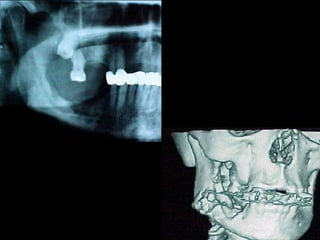

Diagnóstico diferencial

Schwannoma del trigémino, en el cuerpo o en cualquiera de

las ramas.

Schwannoma o Neurilemoma de la Mandíbula Carlos Guillermo Rodríguez Torres* * Odontólogo, Universidad

Javeriana, Santafé de Bogotá, Colombia; Centro de Radiodiagnóstico, Clínica Dental de la Universidad de